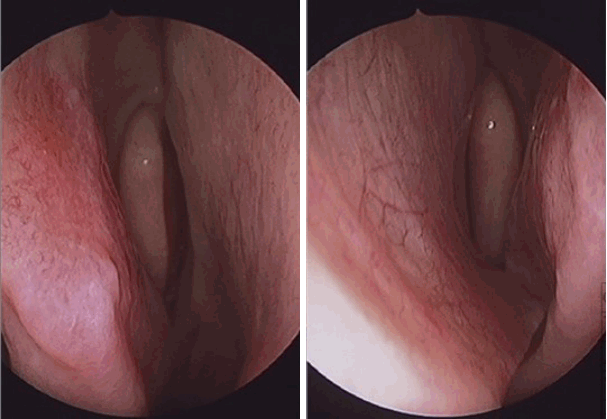

특이 병력이 없는 24세 남자 환자가 1년 전부터 발생한 우측 비폐색 및 간헐적인 수양성 비루, 후비루를 주소로 내원하였다. 비내시경 소견상 좌측으로 편향된 비중격 만곡 및 돌출된 비중격 돌기(septal spur)가 관찰되었고 좌측 하비갑개는 돌출된 비중격 돌기로 인해 함몰되어 있었다(Fig. 1). 타원에서 촬영했던 cone beam CT상에서도 좌측으로 편향된 비중격 및 좌측으로 돌출된 비중격 돌기를 확인할 수 있었으며 부비동염은 관찰되지 않았다(Fig. 2A). 피부 단자 검사는 음성 소견으로 확인되었고, 음향 비강 통기도검사상 좌측 비강이 하강하는 W 모양으로 우측에 비해 좁아져 있는 소견이 확인되었다(Fig. 3A). 상기 소견을 종합해보았을 때 좌측으로 편향된 비중격 만곡증 및 우측의 보상성 하비갑개 비대로 인한 비폐색으로 진단하였으며, 이에 대해 비중격 수술을 계획하였다.

Endoscopic finding of nasal cavity before septoplasty showing septal deviation and spur toward the left nasal cavity with dimpled left inferior turbinate.